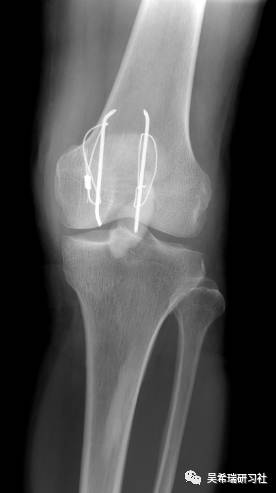

髌骨手术后继发感染40天髌韧带外露

TIPS:清创后再固定伤口用抗生素骨水泥感染得到控制后皮肤牵张闭合伤口2个月内手法松解关节,骨牵引维持5天